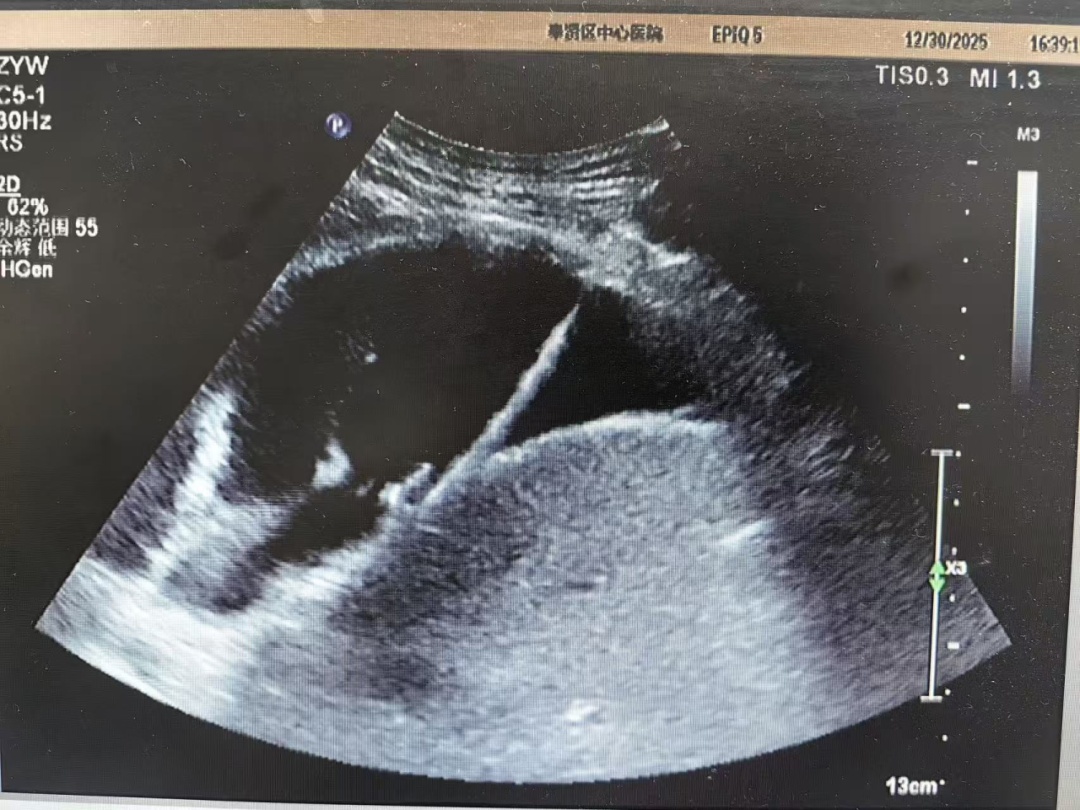

面对这一难题,胸外科迅速启动多学科协作,联合超声医学科进行会诊。经过深入讨论,团队果断决定采用“超声实时引导下胸腔穿刺引流术”,以精准影像为“导航”,实施安全引流。

术中,超声医学科吴涛主治医师仔细扫描,精准锁定积液范围最宽、最适合穿刺的区域,并在体表做出标记,精确测量进针路径与深度。随后,胸外科宋嘉文医师接过“接力棒”,在超声影像的实时“导航”下,将穿刺针稳稳地沿着预定路径送入,精准无误地直达“目标水囊”。一次成功!约800毫升浑浊的积液被顺利引出,患者术后胸闷气促症状得以迅速缓解。